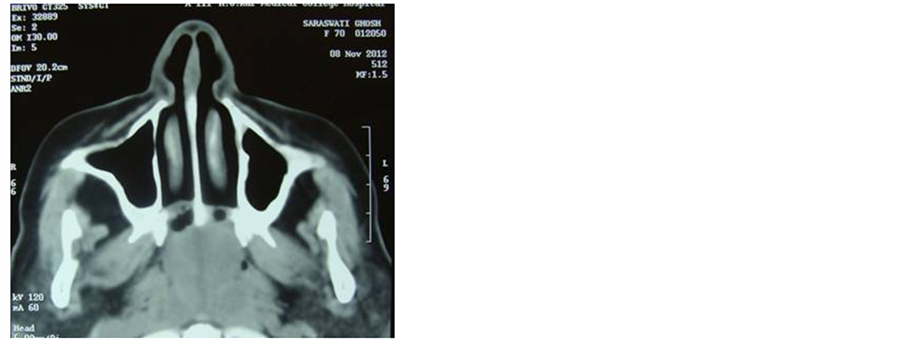

A head and neck CT scan showed an ill defined heterogeneously enhancing soft tissue attenuating polypoid mass within the nasopharyngeal cavity (Figure 1). In the posterior aspect of the mass evidence of porous erosion is seen in anterior margin of the basi-sphenoid. The mass has occluded the posterior nasal air spaces and nasopharynx. The soft palate is thickened and inseparable from the mass superiorly. The pterygoid muscles and adjacent fat planes are maintained. No intrasphenoid or intracerebral extension of the mass was seen. The paranasal sinuses are well aerated and clear. Other routine investigations are within normal limits.

Figure 1. Coronal and sagital section CT scan showed (plain and contrast-enhanced) heterogeneously- enhancing soft tissue lobulated mass in the nasopharynx with evidence of bone erosion at the roof of nasopharynx (clival base).